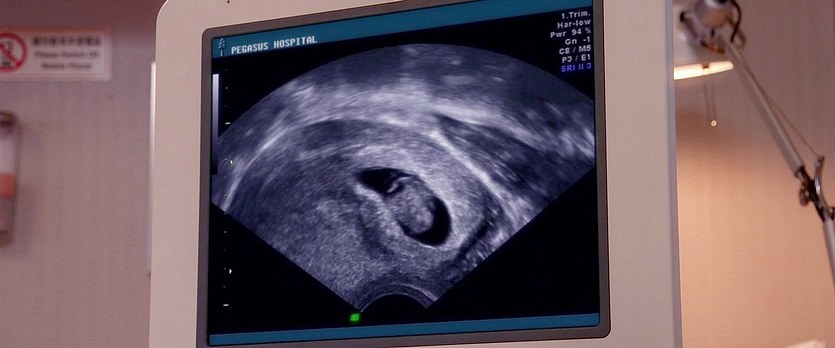

六福喜事

圖片名稱:Hello.Babies.2014_05664

圖源尺寸:Blu-ray 1080p